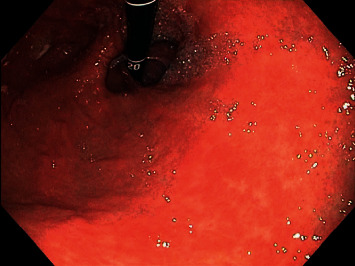

胃假性黑素病是一种良性疾病,其特征是胃壁内上皮下巨噬细胞内的色素沉积。这种情况的发生是罕见的,假性黑色素病更常发生在十二指肠黏膜。胃粘膜内的假性黑色素瘤病例很少报道。我们报告一个病例86岁的女性谁提出了恶化缺铁性贫血有关胃肠道出血。她的内镜检查显示胃内有斑点状的深色色素沉着,经组织学检查证实为假性黑色素病,色素铁染色呈阳性。

Gastric pseudomelanosis is a benign condition that has been characterized by pigment deposition within subepithelial macrophages inside the stomach wall. Occurrence of the condition is rare, with pseudomelanosis occurring more often within the duodenal mucosa. Few cases have reported pseudomelanosis within the gastric mucosa. We report a case of an 86-year-old female who presented with worsening iron deficiency anemia concerning for gastrointestinal bleeding. Her endoscopic evaluation was remarkable for a speckled pattern of dark pigmentation within the stomach, confirmed to be pseudomelanosis by histologic evaluation with pigment showing positive staining for iron.